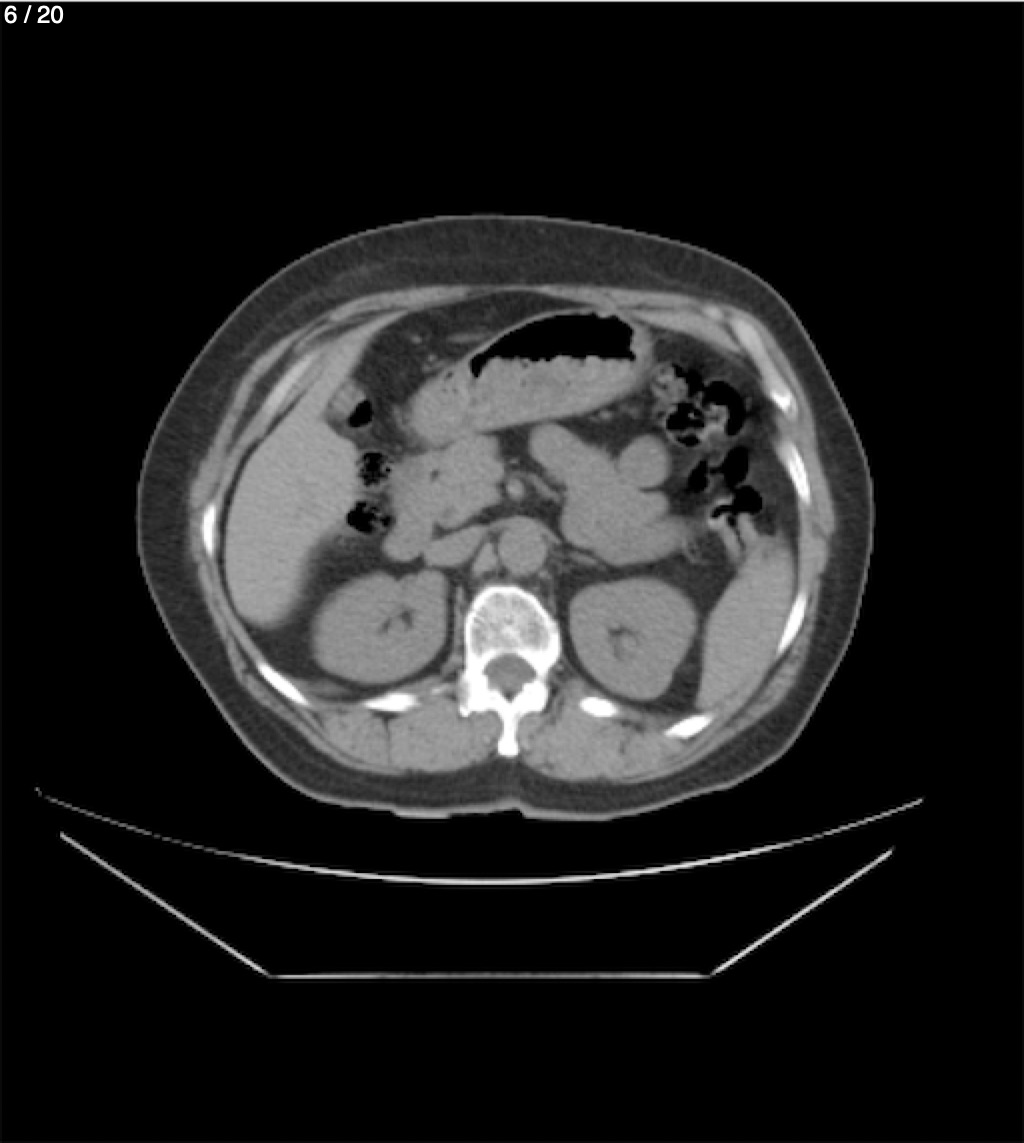

Maria Enrique Giron Dominguez63A - T.C Abdomen Simple